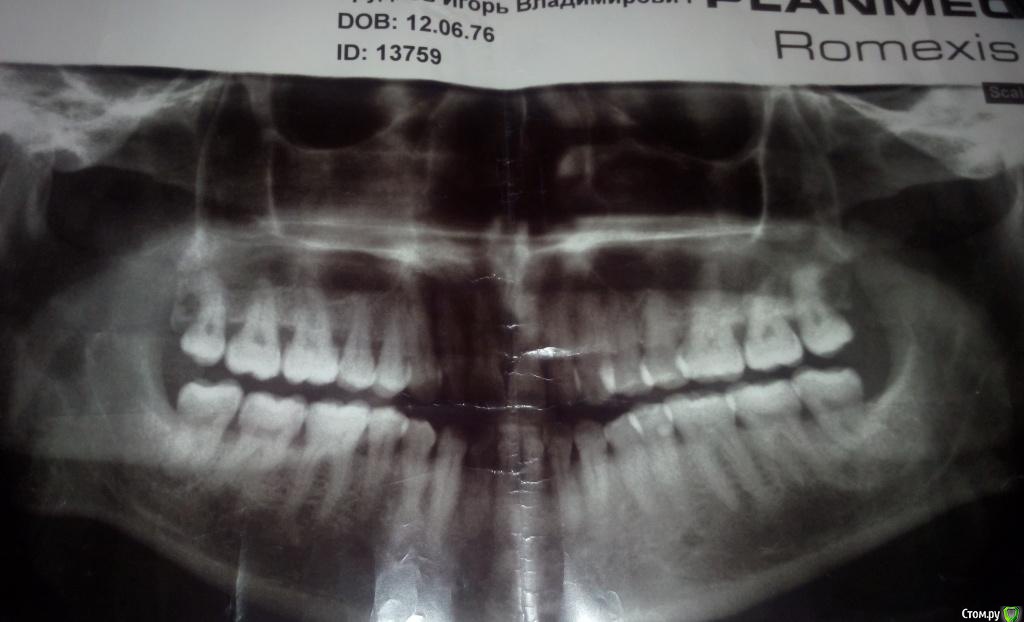

Игорь Гр. Опубликовано 6 ноября, 2015 Автор Поделиться Опубликовано 6 ноября, 2015 (изменено) Здравствуйте,выложите снимки http://forum.stom.ru/topic/20613-sovety-patcientam-obiazatelno-k-prochteniiu/Простите, но я вроде прикрепил снимки. Могу добавить только панораму. Извиняюсь за качество, но что есть ))). Изменено 6 ноября, 2015 пользователем Игорь Гр. Ссылка на комментарий

red_butler Опубликовано 7 ноября, 2015 Поделиться Опубликовано 7 ноября, 2015 Я назначаю АБ терапию только в обострение. На снимке все не так уж плохо. Удалил бы восьмые зубы и ограничился закрытым кюретажем. Но для полного ответа, нужен очный осмотр и зондирование пародонтальных карманов.На снимке не совсем понятно - на 1.6 зубе нависает пломба или камни. Ссылка на комментарий

Игорь Гр. Опубликовано 7 ноября, 2015 Автор Поделиться Опубликовано 7 ноября, 2015 Вот и мне не хочется пить антибиотики, еще и доза большая (начнешь лечить зубы, испортишь кишечник). Но и не доверять опыту врача вроде как нет причин. Вот сижу и не знаю, что делать. А по поводу зуба 1,6, вроде у меня пломб нет Ссылка на комментарий

IvanK Опубликовано 7 ноября, 2015 Поделиться Опубликовано 7 ноября, 2015 вроде у меня пломб нет значит камни) Ссылка на комментарий